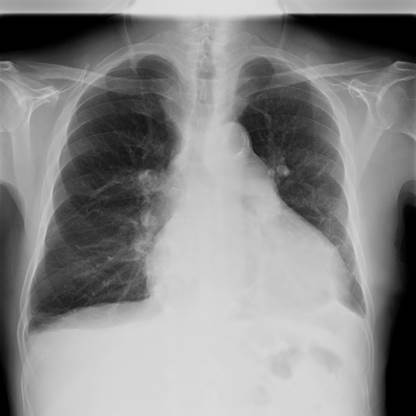

Se presenta el caso de un hombre, de 76 años, fumador y con diabetes tipo 2 en tratamiento con metformina, que acude a urgencias por disnea y edemas en las extremidades inferiores (EEII). En la exploración física presenta crepitantes bibasales a la auscultación pulmonar y edemas bimaleolares en EEII. En la analítica destaca un NT-proBNP de 715,0 pg/mL (normalidad: 0-450). También se realiza una radiografía de tórax con un índice cardiotorácico aumentado y pequeño derrame pleural bilateral (figura 1). Es dado de alta con diagnóstico de «primera descompensación de insuficiencia cardíaca sin datos de alarma» con tratamiento con furosemida, vía oral, 60 mg/día.

El ECG puede ser normal, aunque también pueden aparecer cambios inespecíficos del segmento ST y bajos voltajes. En la radiografía de tórax se observa cardiomegalia. Para su diagnóstico inicial se recurre normalmente a la ecocardiografía. Posteriormente, se puede ampliar el estudio con RM, TC o PET. Pero la caracterización definitiva del tumor requiere obtener muestras para su estudio anatomopatológico5.